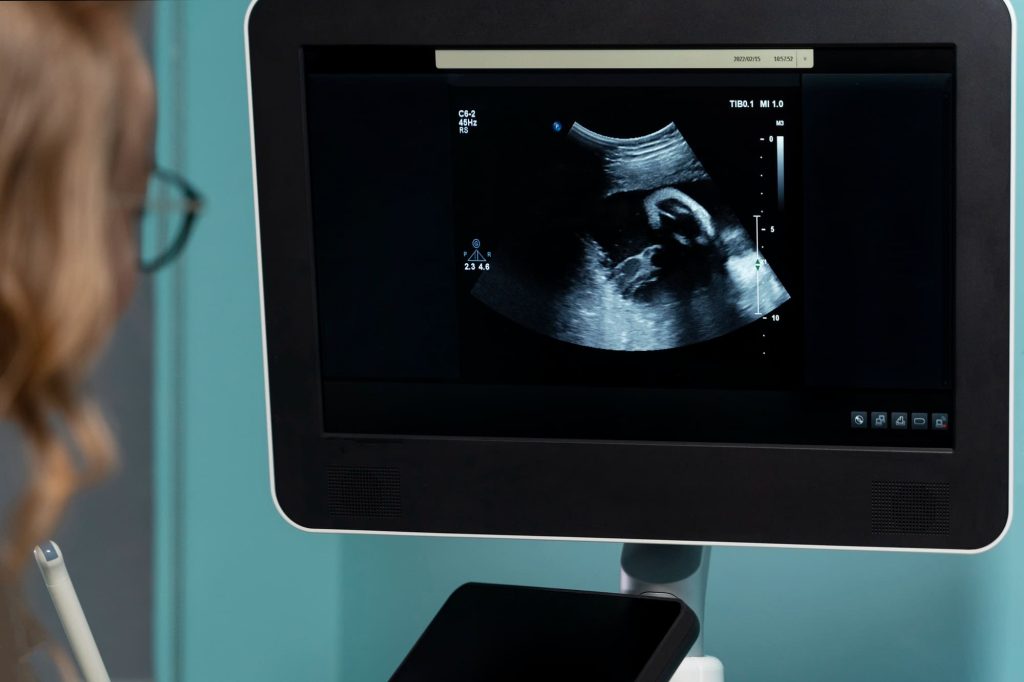

Femland Private Medical Clinic provides professional pregnancy scans to help confirm pregnancy and monitor early development. Ultrasound technology uses safe sound waves to create images inside the body and does not involve radiation.

The ultrasound procedure is safe, painless, and quick. A healthcare professional uses a handheld scanning device placed on the abdomen to produce images of the uterus and pregnancy.